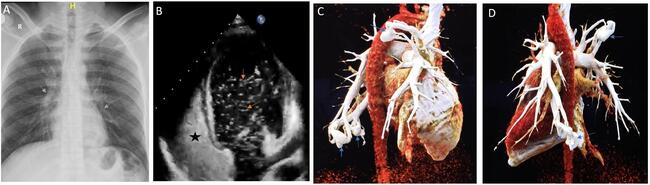

Chest x-ray revealed soft tissue masses in the right upper and left lower lung zones (Figure A, gray arrows). Transthoracic echocardiography revealed normal biventricular function with no shunt lesion. After 3 cardiac cycles, contrast saline echocardiography showed bubbles (Figure B, orange arrows) in the left-sided chambers, which raised suspicion of a pulmonary arteriovenous malformation (PAVM) (Figure B, the black asterisk represents dense bubble contrast in the right atrium [RA] and right ventricle [RV]; Video 1). Pulmonary computed tomography angiography with 3-dimensional reconstruction confirmed the presence of 3 PAVMs: 2 in the left lower lobe (19 x 15 mm and 7 x 5 mm) and 1 in the right upper lobe (20 x 15 mm) (Figure C and D, blue arrows). Genetic testing for hereditary hemorrhagic telangiectasia was negative.